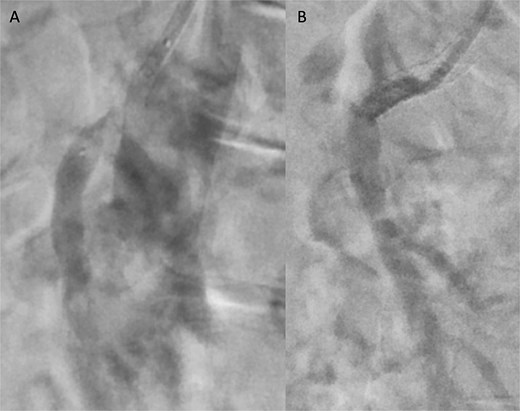

Angiographic images before (A) and after (B) thrombectomy of the superior mesenteric artery (SMA).

Angiographic images before (A) and after (B) primary stenting of SMA ostium using a 6 × 39 mm Advanta® stent with proximal flare.